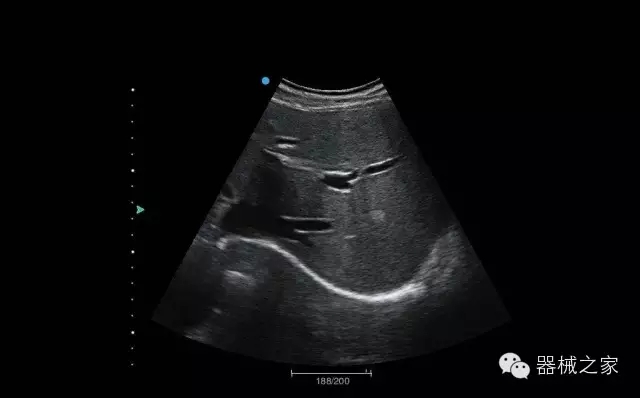

經(jīng)典產(chǎn)品:Acclarix AX8

臨床圖片賞析

睪丸低速血流

臍帶血流

頸動脈頻譜

產(chǎn)品特點(diǎn)

·新視界、高效能、新體驗(yàn);

·別具匠心的獨(dú)特設(shè)計(jì)、創(chuàng)新工作流、強(qiáng)大的功能組合以滿足POC圖像的需求;

·15英寸高分辨率顯示器;

·10.1英寸防指紋觸摸屏;

·獨(dú)一無二的觸控式軌跡球;

·超聲模塊的便攜式設(shè)計(jì);

·128物理通道;

·UPS持續(xù)供電;

多項(xiàng)前沿圖像技術(shù)

·復(fù)合成像 波束合成 頻率復(fù)合 噪聲抑制等;

穿刺針增強(qiáng)技術(shù)

·顯著增強(qiáng)針體 清晰識別結(jié)構(gòu)、位置等比鄰關(guān)系;

多種成像模式

·梯形成像 寬景成像 3D成像 特征成像等;

CFDA注冊證編號

·粵械注準(zhǔn)20152230912